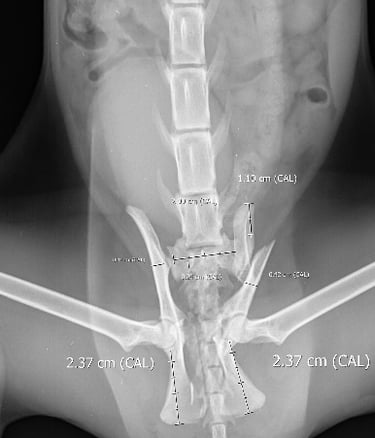

On presentation, she was unable to bear weight on her pelvic limbs. Withdrawal reflex and nociception were present, with normal proprioception in the right pelvic limb but delayed in the left. X-rays confirmed a right sacroiliac luxation, a left oblique ilium body fracture, a left ischium fracture involving the acetabulum, and bilateral pubic fractures (Figs. 1 and 2).

Fig. 1